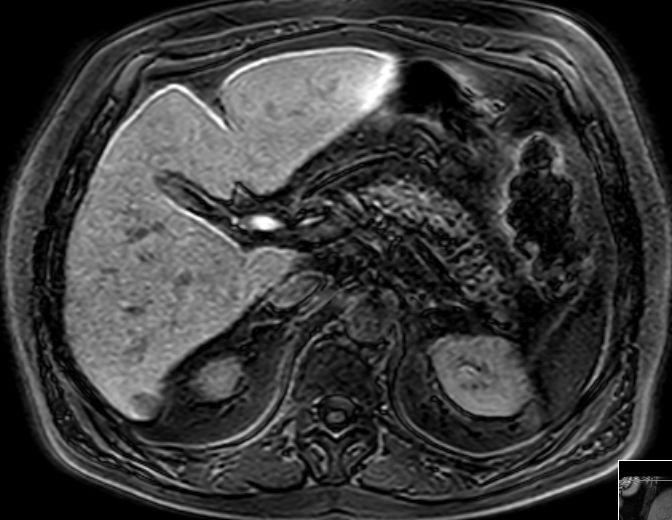

Am Unterrand des rechten Leberlappens vom 6. zum 7. Lebersegment ein 17mm signalabgesenkter, subkapsulär gelegener Herd.![]() | ||